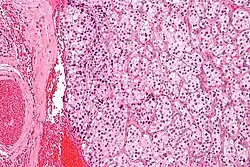

Micrograph of a carotid body tumor (a type of paraganglioma)

Micrograph of a carotid body tumor with the characteristic Zellballen. H&E stain.

The paragangliomas appear grossly as sharply circumscribed polypoid masses and they have a firm to rubbery consistency. They are highly vascular tumors and may have a deep red color.

On microscopic inspection, the tumor cells are readily recognized. Individual tumor cells are polygonal to oval and are arranged in distinctive cell balls, called Zellballen.[9] These cell balls are separated by fibrovascular stroma and surrounded by sustentacular cells.